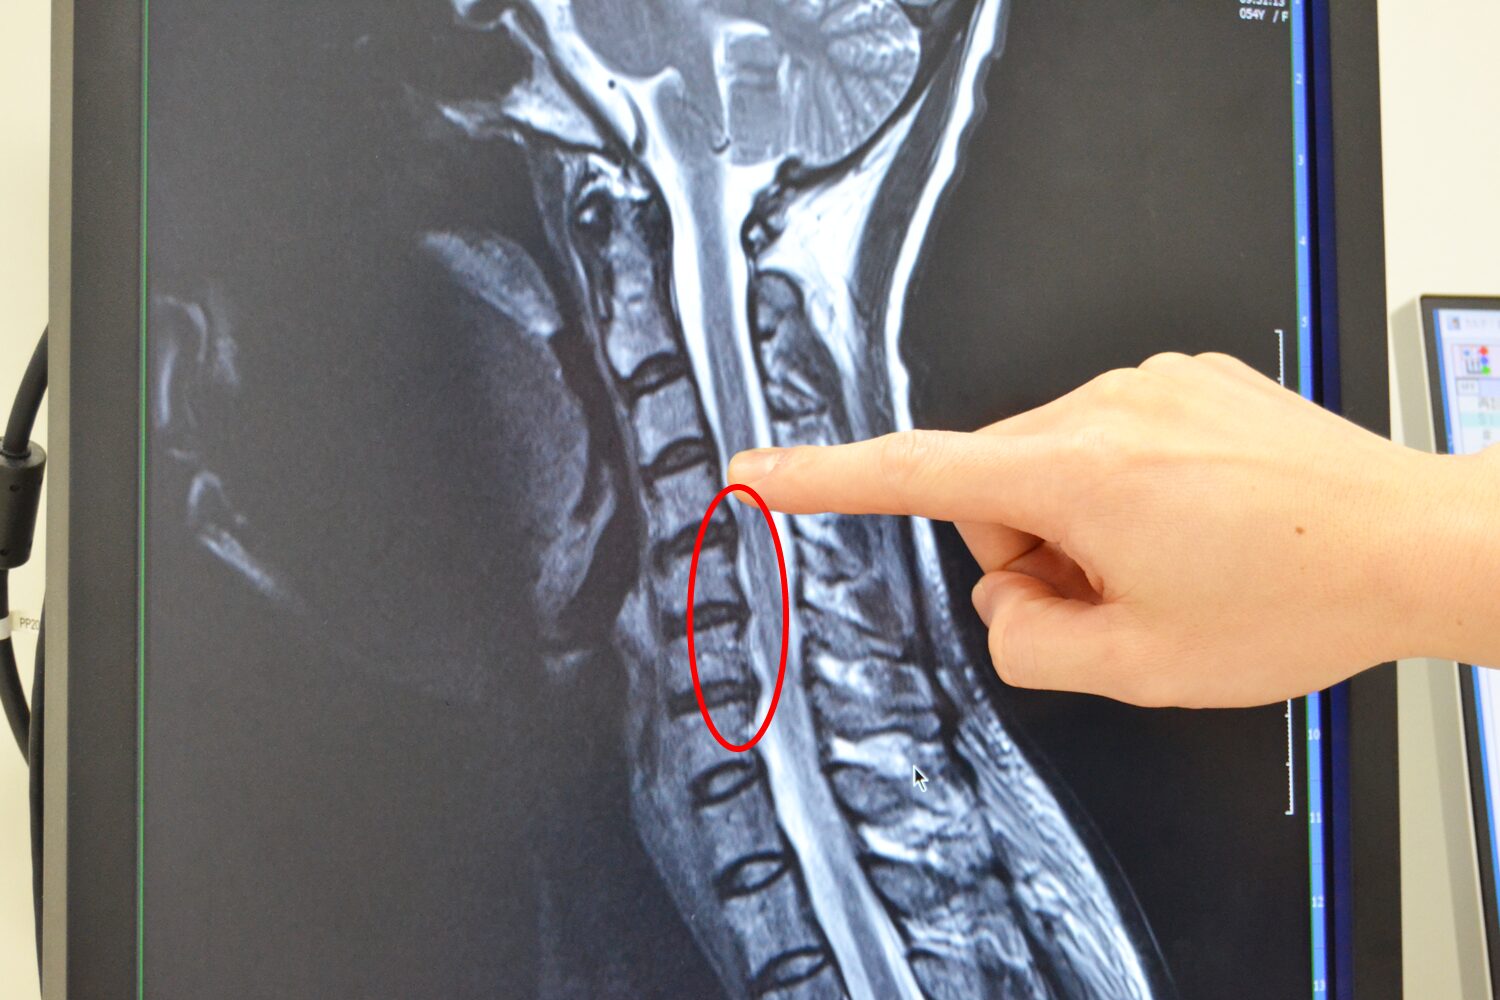

頚椎症のMRI画像

こちらは同じ方のMRI画像です。首の骨はレントゲンと同じように後ろに曲がっていることがMRIでも確認できます。また、背骨の間から少し膨らんでいるものが出ていて、神経に対して少しだけヘルニアっぽくなっているのも確認できます。背骨と背骨の間には繊維輪と髄核(ずいかく)から構成されている椎間板というクッション材があるのですが、これが少しだけ膨らんででてきています。このように、MRIでは骨が神経を圧迫しているかどうかや、ヘルニアがあるか、頚椎症による神経根症があるかどうかなどがわかります。